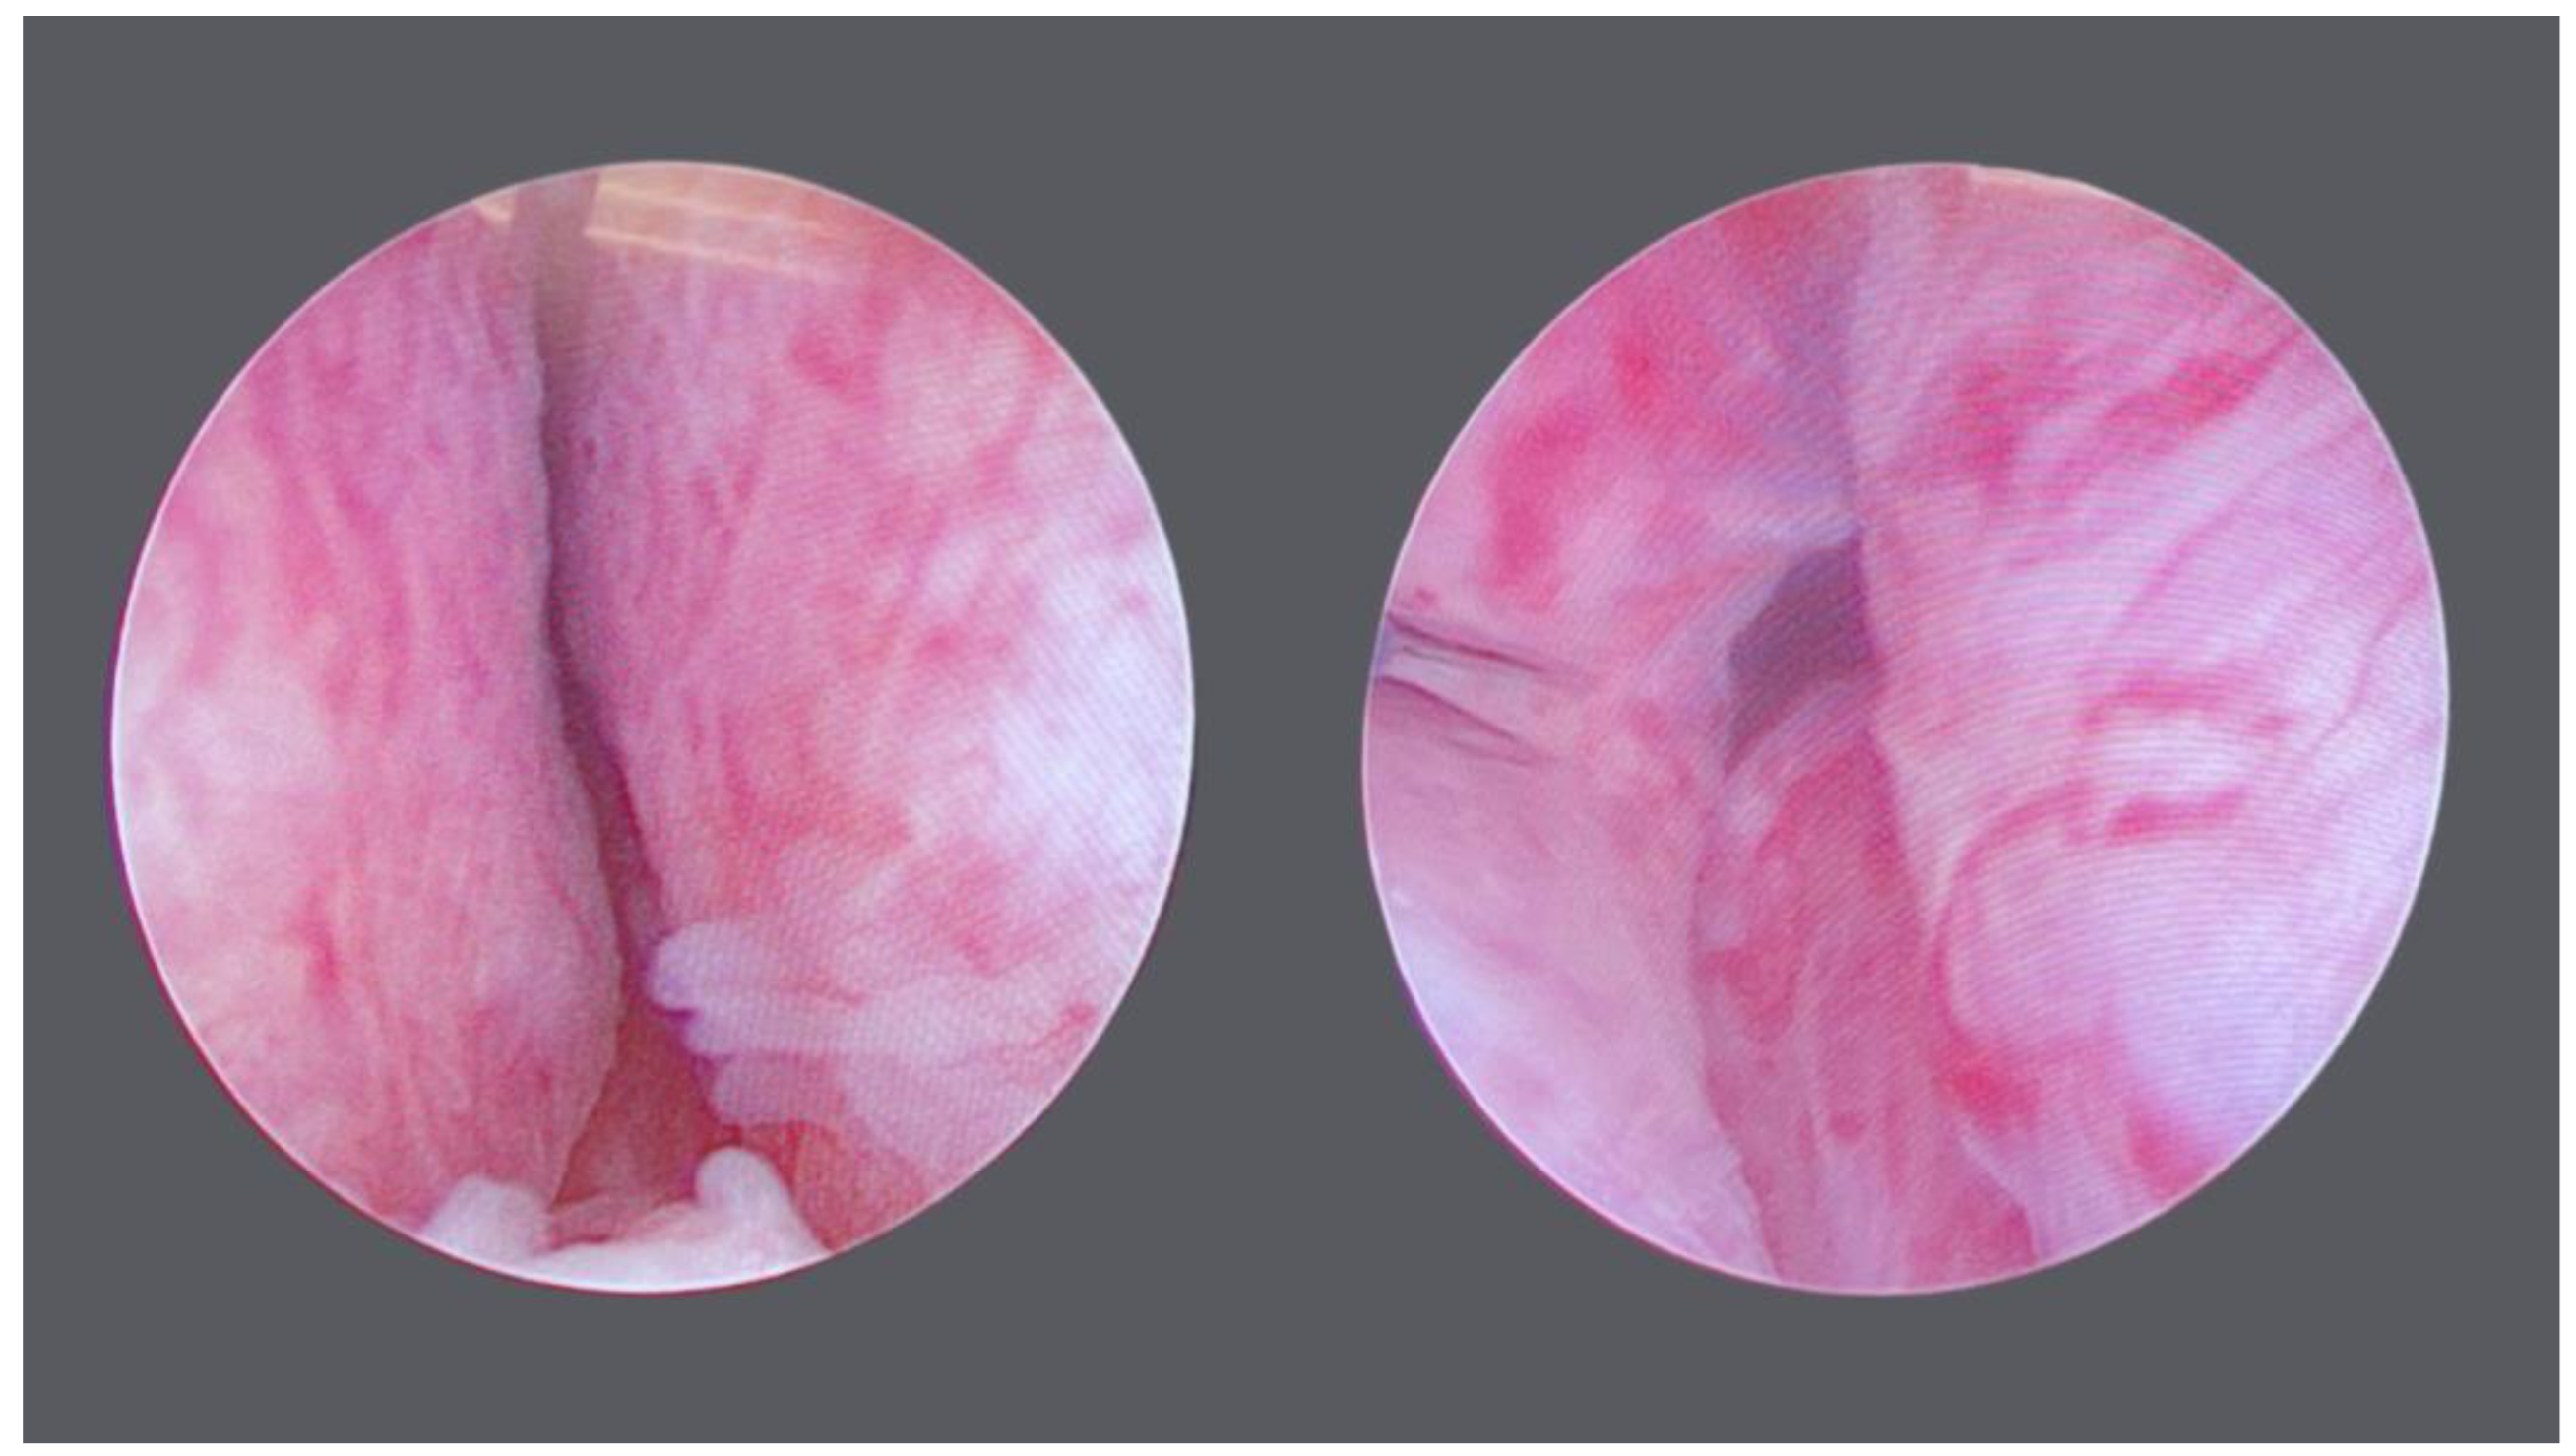

- McNicholas, T.A.; Woo, H.H.; Chin, P.T.; Bolton, D.; Arjona, M.F.; Sievert, K.-D.; Schoenthaler, M.; Wetterauer, U.; Vrijhof, E.J.; Gange, S.; et al. Minimally invasive prostatic urethral lift: Surgical technique and multinational experience. Eur. Urol. 2013, 64, 292. [Google Scholar] [CrossRef]